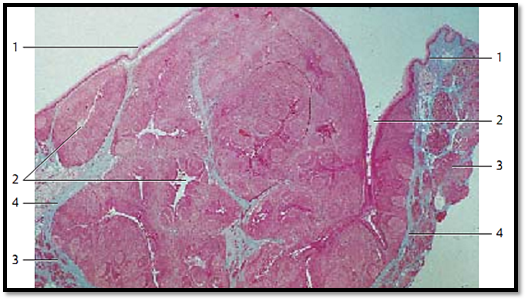

Palatine Tonsil

The palatine tonsils are covered by the mucous membranes of the oral cavity 1 (multilayered nonkeratinizing squamous epithelium). The tonsils show about 15–20 deep, of ten branched crypts 2 ( fossulae tonsillares ). The crypts extend deep into the lymphoreticular tissue of the tonsil. A wall of lymphoreticular tissue with secondary follicles surrounds each crypt. A connective tissue capsule separates the palatine tonsil from the surrounding and the Killian muscle. In the figure, at the right and left, the muscles of the palatopharyngeal arch 3 are cut.

1 Epithelium of the oral cavity

2 Tonsillar crypts

3 Killian muscle, musculature of the palatopharyngeal arch

4 Connective tissue capsule

Stain: azan; magnification: × 10